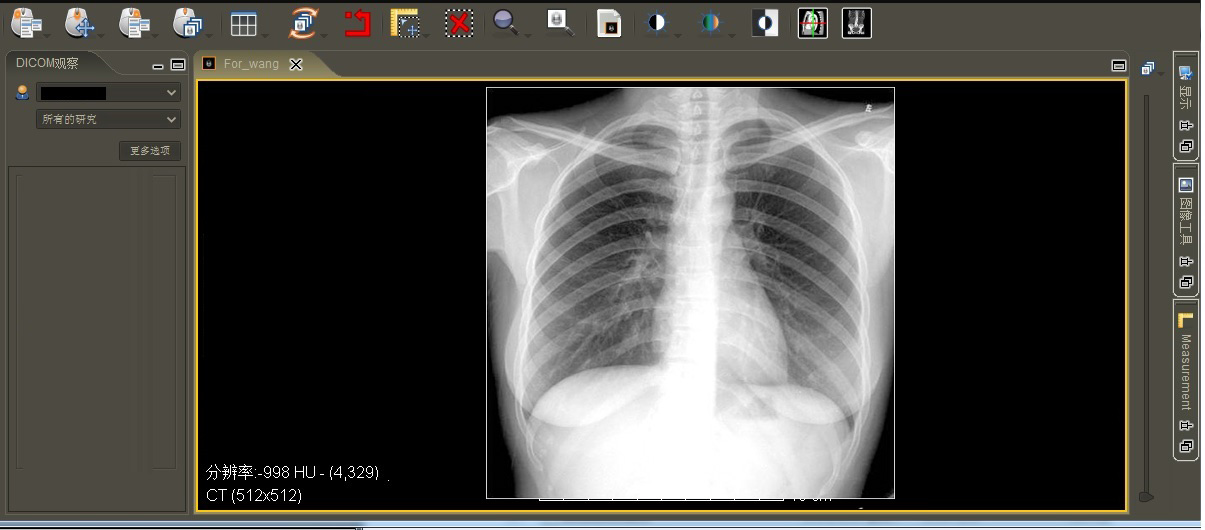

医学影像诊断实验与考试系统主要用于高校医学影像类专业或培训机构影像诊断培训与考核之用,系统中备有较为丰富的图像资源和试题库,方便学生影像诊断与成绩测试。

4.影像处理: 支持DICOM3.0标准,可进行调节窗宽窗位、缩放、测距、旋转、明度调整,图像漫游等DICOM图像处理功能。

6.预存丰富的图库: 万余幅不同病例的图像,分头颈部、胸部、腹部、脊柱、四肢等部分。